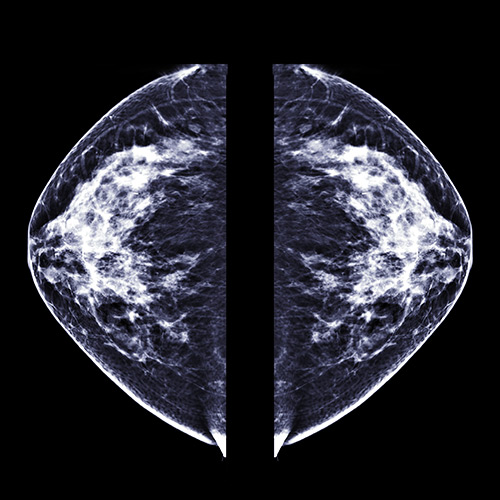

Screening mammograms

Doctors recommend annual screening mammograms to begin at age 40 for people with an average risk of developing breast cancer. Mammograms are critical in reducing the number of women who die from breast cancer.

At NewYork-Presbyterian cancer screening centers, digital and 3D mammography, also called tomosynthesis, are used to capture and display X-ray images on a computer. These images can be viewed from different angles. 3D mammography can take a deeper look into the breast tissue.

During a mammogram, you will stand in front of the X-ray machine while your breast is placed between two plastic plates. These plates flatten your breast so a clear picture of the breast tissue can be seen. Sometimes more than one screening mammogram might be done if better clarification is needed to show tumors or other abnormalities which could indicate cancer. Mammograms have proven useful in diagnosing breast cancer before any signs of the disease have become apparent.